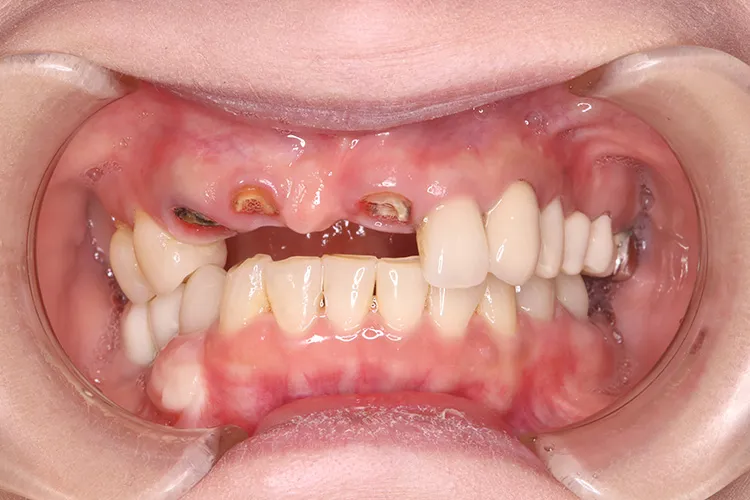

歯ぎしり・食いしばりが強い方の治療ケースです。全体的に歯が擦り減り正面から見て下の歯が見えないほど噛み合わせの高さが失われており、顎関節にも症状がでていました。ヒビが入って保存不可の歯を抜歯しインプラントを計5本埋入し、前歯・臼歯にインプラント土台のブリッジを入れることで噛み合わせの高さを回復しました。古い金属の被せ物もジルコニアでやりかえました。噛み合わせの高さが改善したことで顎関節症状もなくなり快適に過ごされています。歯ぎしりがある方は、夜間のナイトガード装着が必要になります。